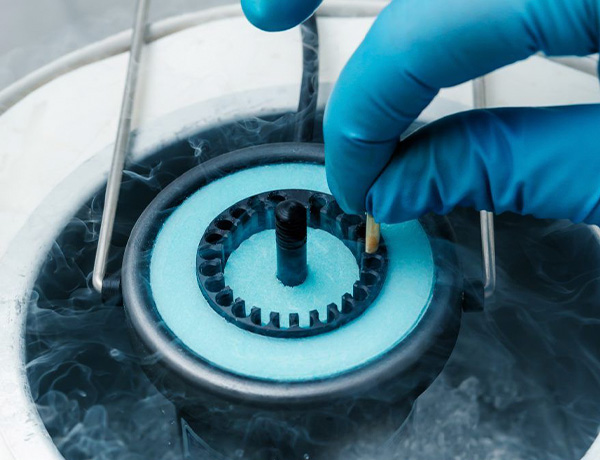

As amostras são coletadas e processadas em laboratório, sendo então armazenadas em nitrogênio líquido a -196°C. O material pode permanecer congelado por tempo indeterminado, e ser utilizado futuramente em tratamentos de reprodução assistida, como a inseminação intrauterina (IUI) ou a fertilização in vitro (FIV/ICSI).

O congelamento é feito em nitrogênio líquido a -196°C, com possibilidade de uso futuro por meio de FIV. Essa técnica traz liberdade reprodutiva e segurança para decisões mais conscientes.

Os embriões são formados a partir da fertilização in vitro (FIV ou ICSI), com óvulos e espermatozoides próprios ou doados. Após congelamento, ficam armazenados por tempo indefinido, podendo ser transferidos ao útero no momento mais oportuno.